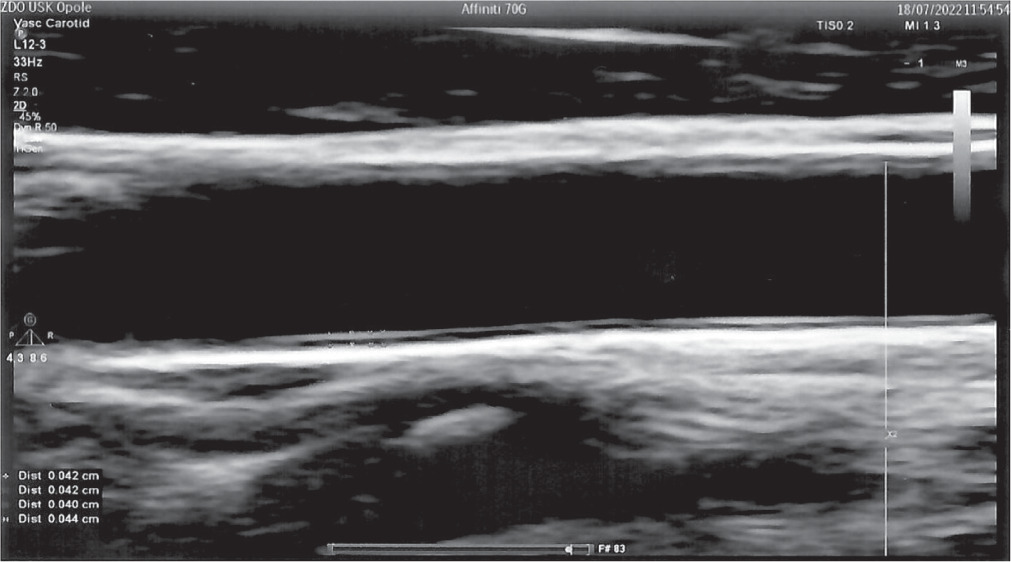

Carotid artery intima and media thickness (cIMT) is considered a structural marker of early atherosclerosis in DM. It depends on metabolic control and increases as the disease progresses, predicting several macro- and microvascular complications [2]. The IMT is measured as the distance between the lumen-intima and media-adventitia interfaces (Fig. 1). The presence of atherosclerotic plaques in the carotid artery is a strong predictor of CVD [15]. Many research papers have used the assessment of cIMT by ultrasound scan (USG) as one of the best methods due to its non-invasive nature, easy accessibility, and high accuracy. USG visualizes the structure of the arterial wall with better resolution than any other imaging. Due to its increasing popularity, as well as the growing number of studies using cIMT measurements, it was necessary to unify the guidelines for the cIMT assessment technique. Examination of the carotid wall should be performed using a high-resolution B-mode system equipped with a linear array transducer > 7 MHz [16].

The first cIMT consensus took place in Mannheim in 2004, and the latest update was in 2011. The paper describes examination procedures in detail. The main cIMT scanning and reading protocol recommendations are as follows: 1. IMT measurement should be performed in a plaque-free region. 2. Measurements can be made in the common carotid artery, carotid sinus, and internal carotid artery. 3. In research studies assessing the thickness of vessel walls, the values obtained from different measurement sites should be documented separately [16].

The cIMT > 0.9 mm is considered too thick, but the highest valid value varies with age (Table II). IMT ≥ 1.5 mm suggests the presence of atherosclerotic plaque [15].